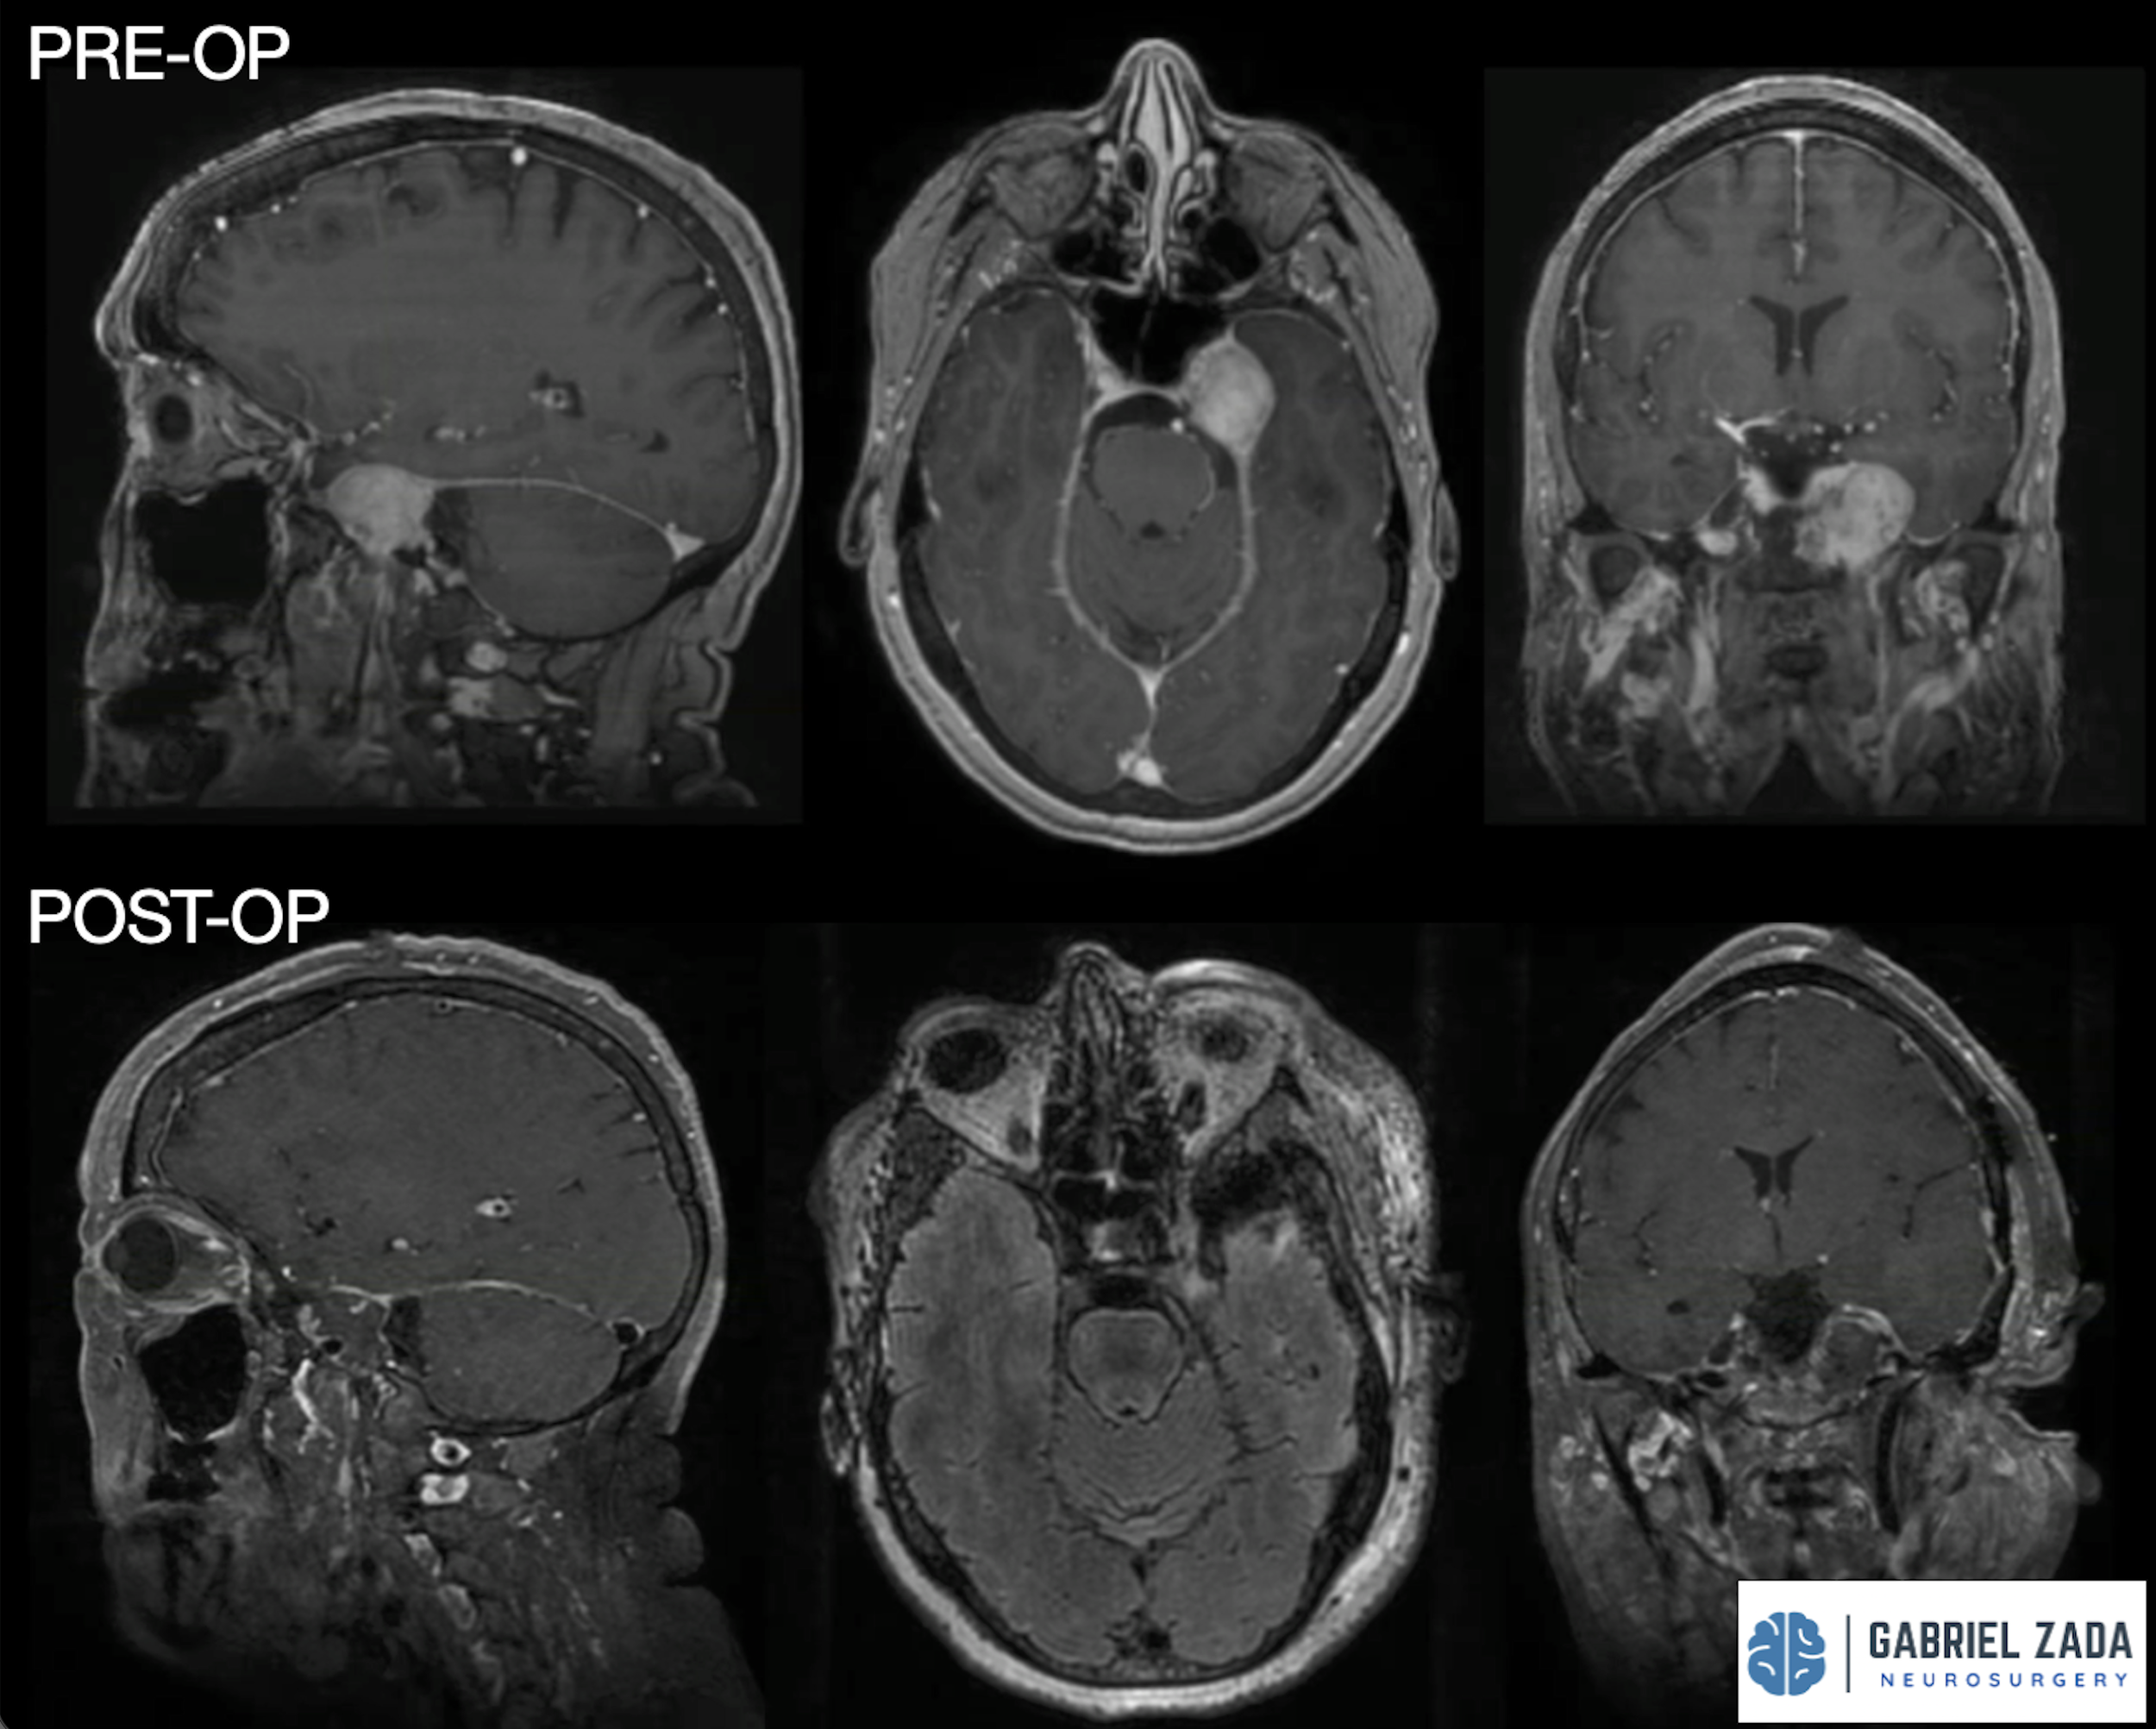

Explore this comprehensive gallery featuring pre‑ and post‑operative imaging of patients with skull‑base tumors treated by Gabriel Zada, MD, MS, FAANS, FACS. These cases highlight Dr. Zada’s expertise in advanced neurosurgical techniques and outcomes.

*Representative cases shown for educational purposes. All images de-identified. Individual results vary.